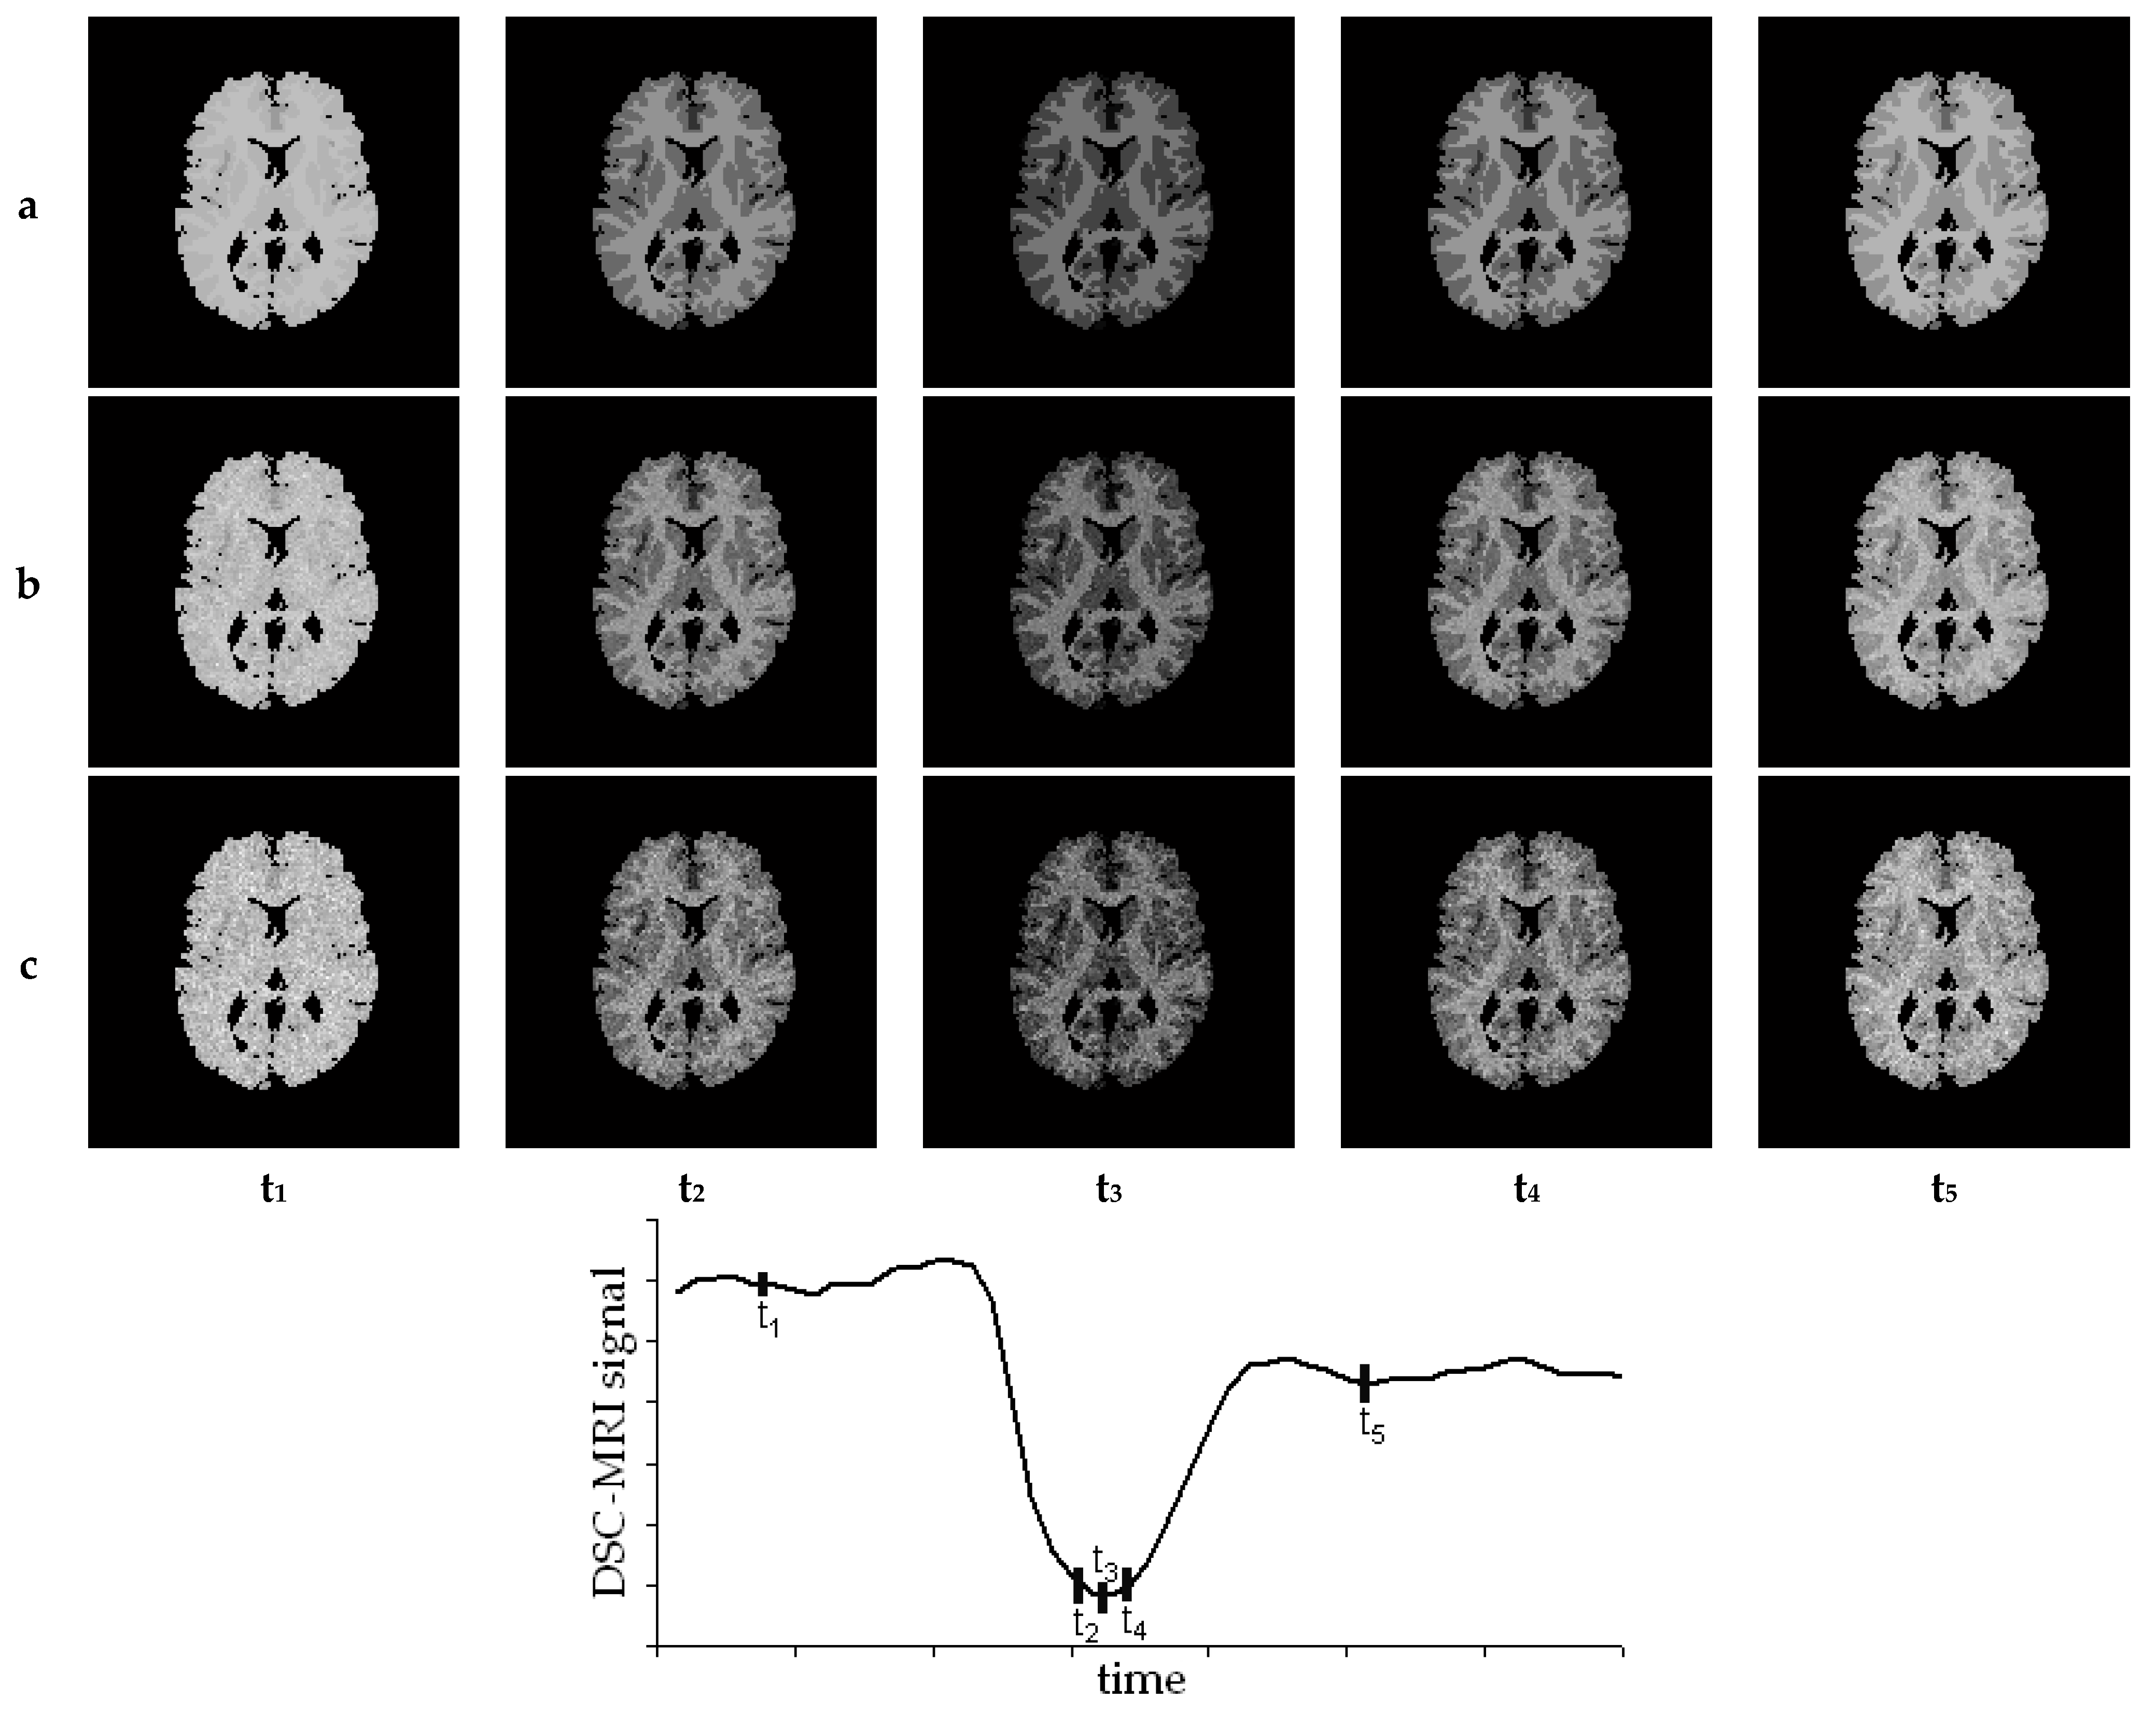

7. Results—Exemplary DSC-MRI Study Models